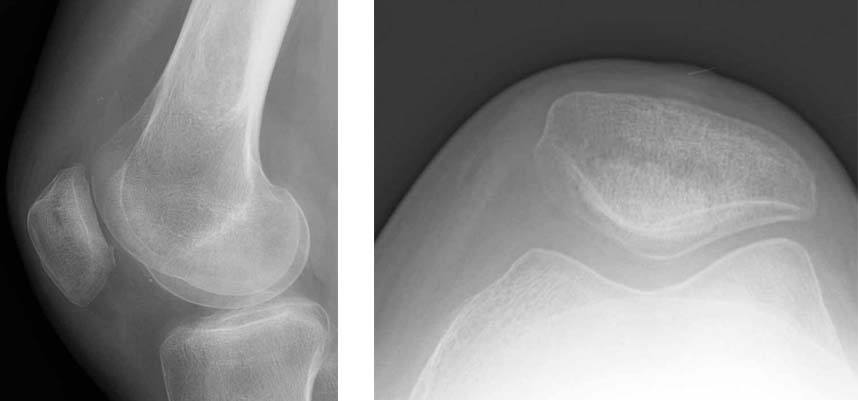

1. These are radiographs of her knee showing minimal arthritis and the presence of the osteotomy plate on the outer aspect of the femur.

7.The final radiographs show the multiple screws used to fix the tibial graft. No fixation was required for the graft on the femur. On the closeup image on the right, one can see the interface between the tibia and the graft (large arrows) as well as the bony surface of the graft on the femur (small arrows). The patient's symptoms of knee pain have nearly fully resolved with the surgery.